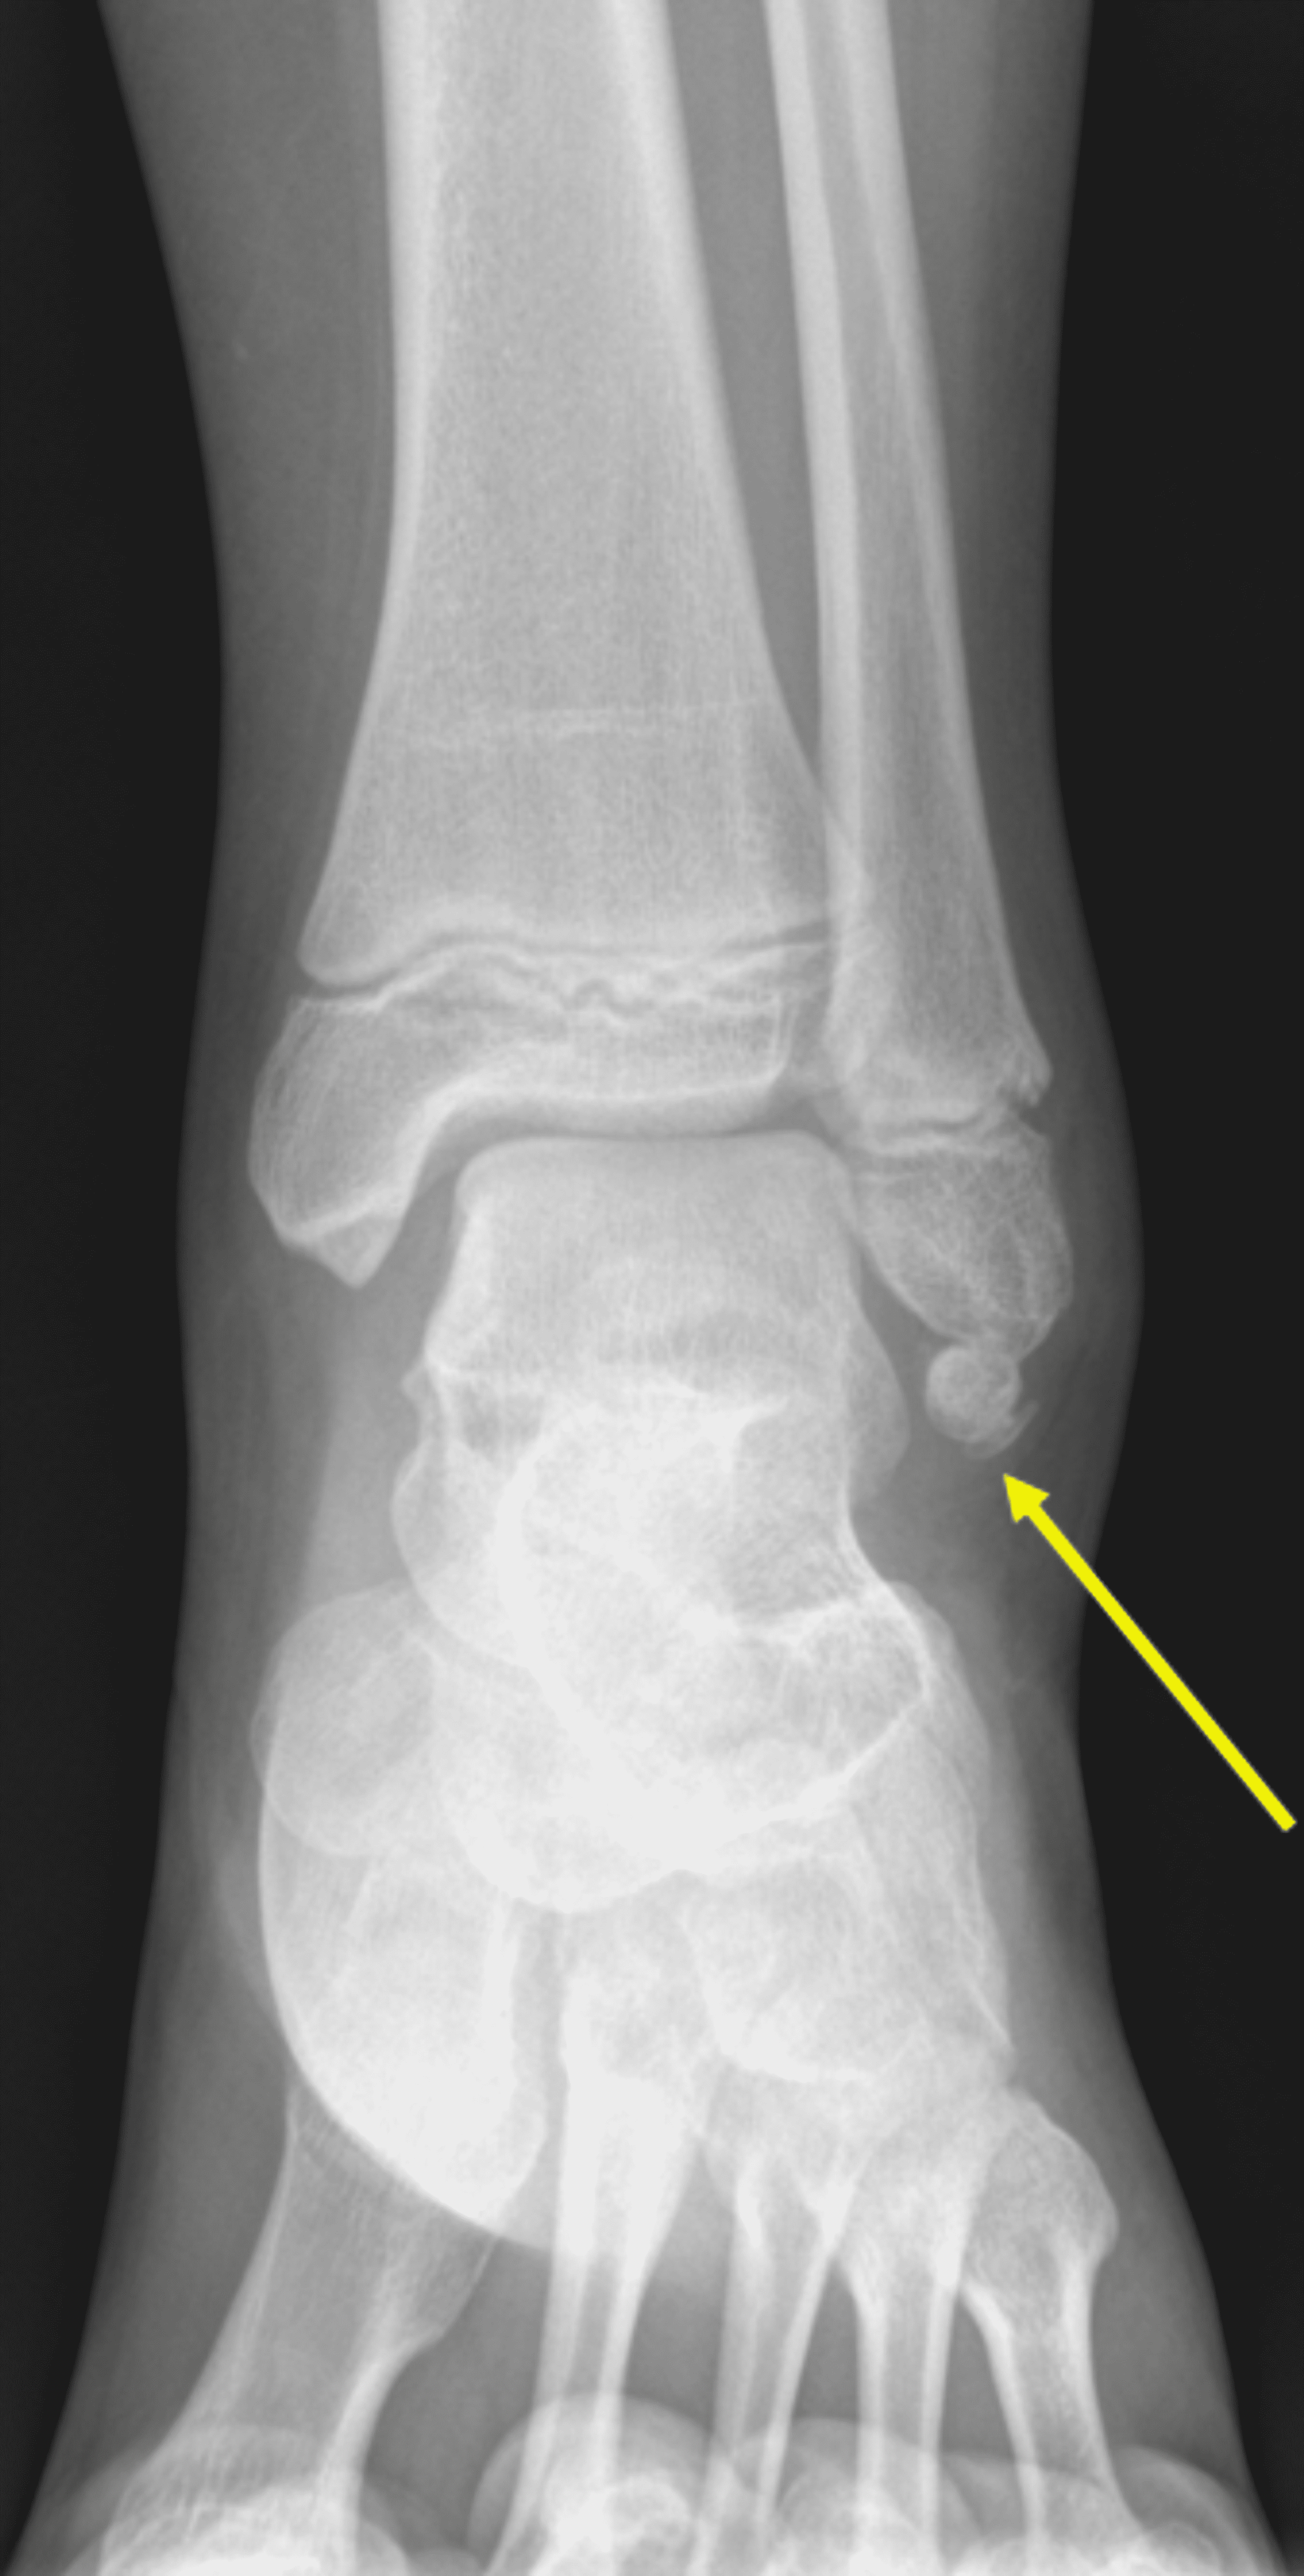

Cureus Optimal Visualization of Os Subfibulare Using 3D Water Accessory Ossicles Radiology They are often noted incidentally during evaluation of foot and ankle injuries, and most can be managed nonsurgically. accessory ossicles and sesamoid bones are frequent findings in routine radiographs of the ankle and foot. our purpose is to review the imaging findings of some of the more common sesamoids and accessory. accessory ossicles of the feet are. Accessory Ossicles Radiology.

Cureus Optimal Visualization of Os Subfibulare Using 3D Water Accessory Ossicles Radiology accessory ossicles are a common radiographic finding about the foot and ankle in children and adolescents. accessory ossicles are usually an incidental finding on radiographs and often. accessory ossicles are supernumerary and inconstant structures. our purpose is to review the imaging findings of some of the more common sesamoids and accessory. They are often noted incidentally. Accessory Ossicles Radiology.